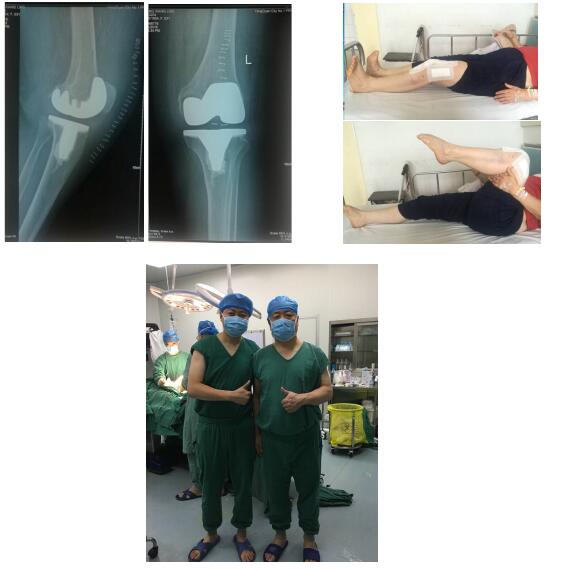

- 2018年7月 由陽泉市第一人民醫院付辛榮主任開展了該醫院首例GKS PRIME 膝關節置換。術后病人很滿意,功能鍛煉良好。

- 2018年1月,由武漢市第三醫院周少懷主任帶領的團隊開展了首例GKS PRIME 膝關節置換手術。